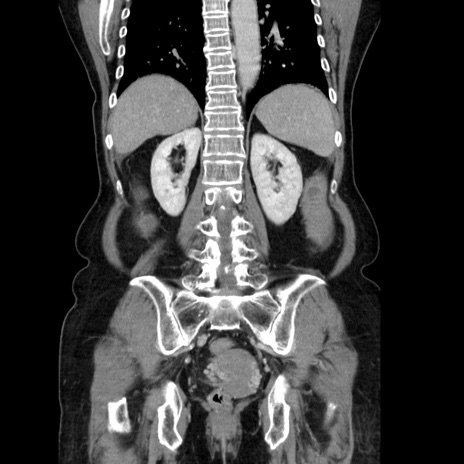

症例5(冠状断像)

【症例】70歳代女性

【主訴】お腹が張る

【現病歴】1週間くらい前から腹部膨満の自覚あり。昨日夜から増悪したため、本日救急外来受診。

【身体所見】意識清明、BT 36.5℃、BP 165/106mmHg、HR 80bpm、SpO2 98%、腹部:膨満、軟、自発痛・圧痛なし、触診にて不快感あり、腸蠕動音:減弱

【データ】WBC 12600、CRP 1.04